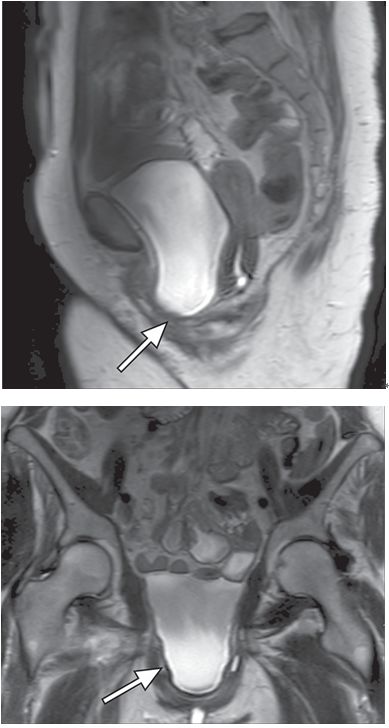

膀胱膨出指膀胱向阴道前壁的膨出。在透视时表现为阴道穹隆的外源性压迫,MRI可以直接观察到膀胱下降到耻尾线以下(图2)。膀胱膨出的原因是盆内筋膜的薄弱或者缺损,常见于多次分娩的女性。正常情况下下尿道几乎是垂直方向走行,但是对于经阴道分挽或子宫切除术后尿道失去支持的患者,尿道在静息或者应力情况下可能会出现向水平方向的旋转,从而导致压力性尿*禁失**。

图2 膀胱膨出。矢状位(A、冠状位(B)的T2WI示膀胱下疝(箭)至耻骨联合以下。注意整个盆底下降